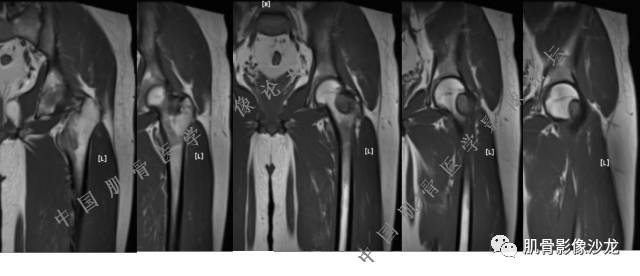

主诉:右髋及右膝部疼痛3月余

现病史:3月前打球时自觉右大腿肌肉拉伤后右髋及右膝部疼痛,自服“活血化瘀”类药物(具体不详)后自觉疼痛缓解,2月前打球时再次扭伤,右髋及右膝部疼痛明显,行走时疼痛加重,自服药物治疗,效果不佳,遂来诊。

葛英霖 20:10 判断恶性程度需要看骨髓内浸润的是肿瘤还是水肿 ,从目前看,骨肉瘤是要考虑的

张小林 20:13 磁共振有双低信号,结合CT确实要考虑有纤维成份。

医影在线 20:13 干骺端溶骨性破坏,边缘模糊,低密度肿块,似有钙化

Echo 20:13 有骨质破坏,边界不清,有软组织肿块,我觉得恶性是要考虑的

Echo 20:23 我个人觉得,17岁男性,病灶发生在原干骺端区域,溶骨性骨质破坏,似有肿瘤骨,有软组织肿块形成,从常见病发生率来说,骨肉瘤还是要考虑的